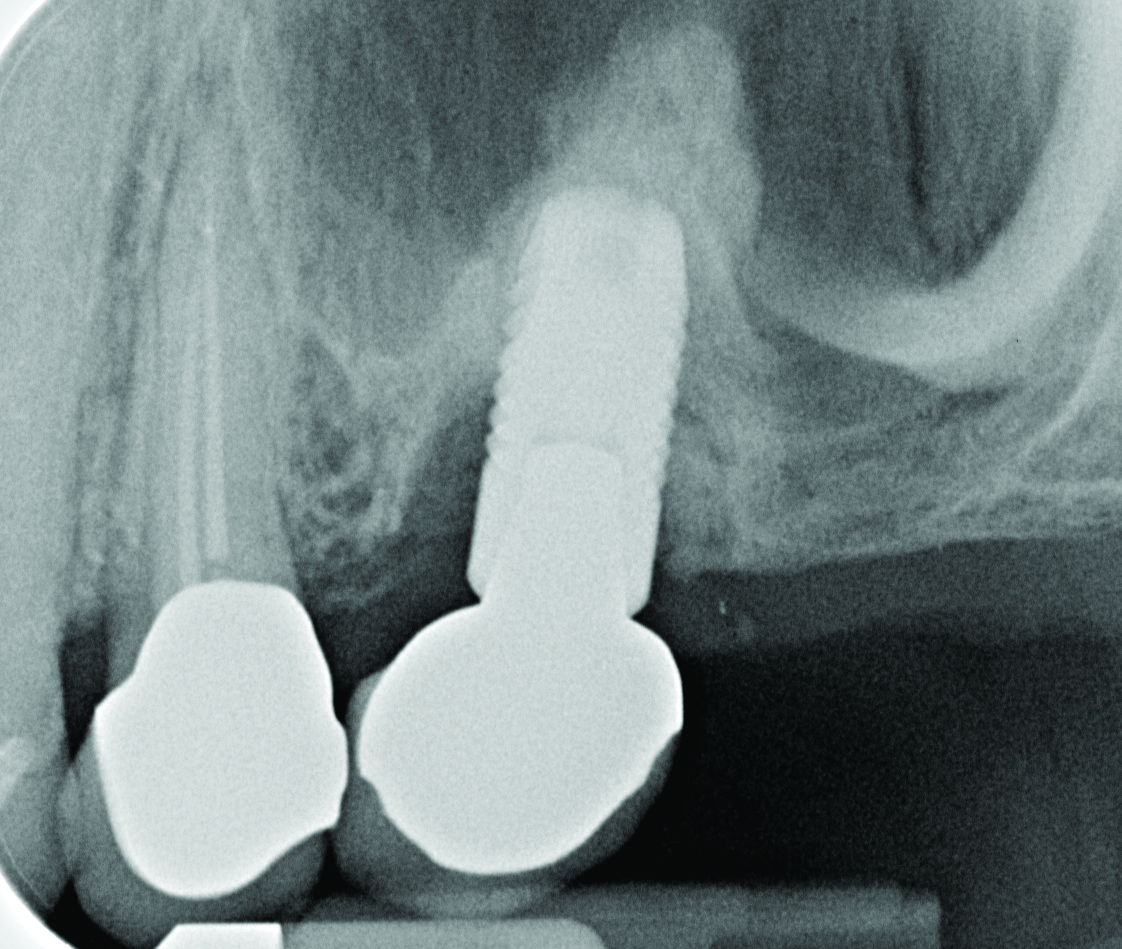

Radiograph of this same area. Note that there is no indication of bone loss and a long abutment collar. Hence, the diagnosis of peri-implant mucositis is given.

Figure 2